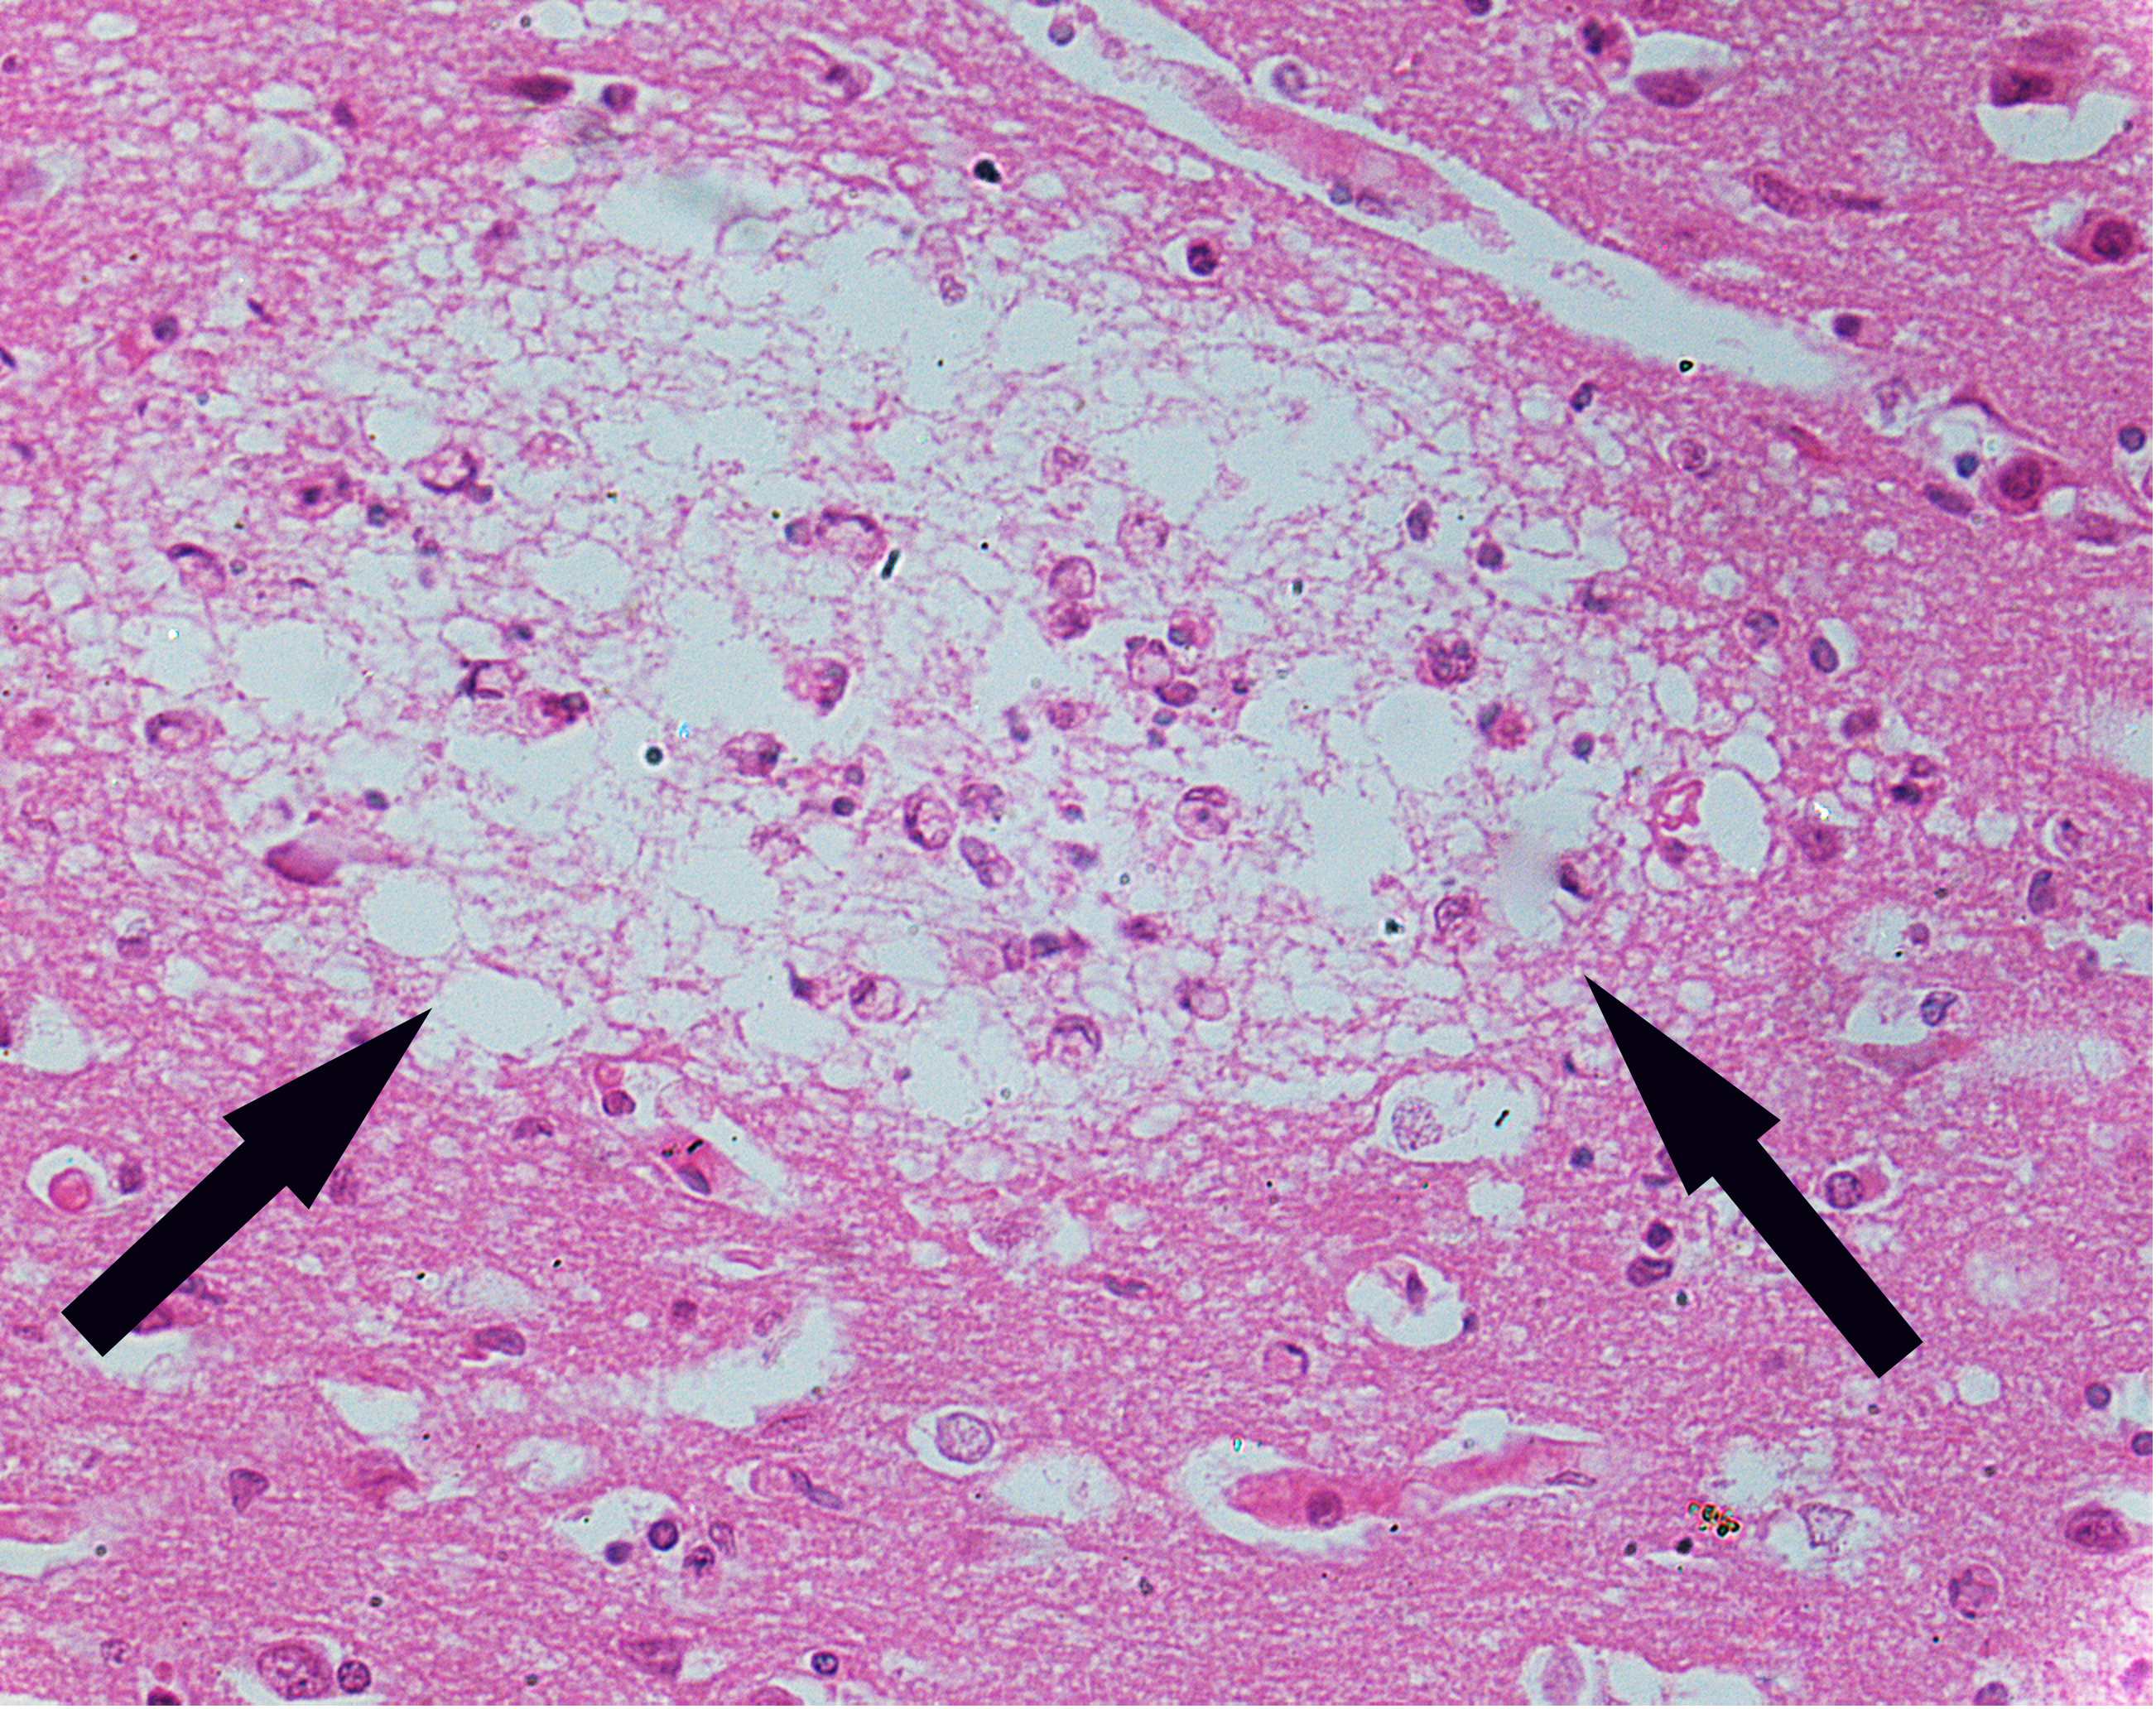

2.Encephalitis type B-liquefied necrosis

2.Encephalitis type B-2